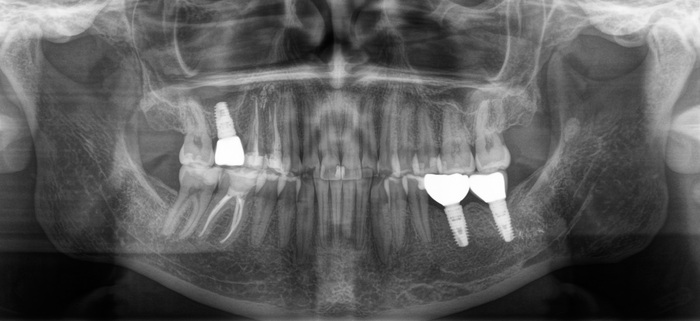

И тут начинается самое интересное. Что такое абатмент мы выяснили из картинки выше, это переходный элемент между коронкой и имлпантатом. Так вот по всем технологиям и нормам он должен быть титановым. Как контрастирует титан на рентгеновском снимке вы можете заметить, посмотрев на имплантат. Видите разницу между 6м и 7м имплантатом?

Так вот абатмент, который вставляется в имплантат из другого материала. Вероятнее всего это кобальт-хромовый сплав. Такие штуки изготавливаются литьевым методом. Все мы знаем, что металл при нагревании расширяется, а остывая сжимается, дает усадку. Соединение имплантат- абатмент должно быть четким. Важны даже микроны. В данном случае наверняка была микроподвижность в этом соединении, высокая нагрузка на винт, в связи с чем он и сломался.

(упд: я так думал изначально)

Часть с резьбой осталась в имплантате

На рентгеновском снимке:

Внутренний конструктив имплантата:

Благо я работаю с профессионалами. Иван Алгазин, наш ортопед, умудрился достать обломок винта, что крайне сложно сделать не повредив принимающую часть в имлпантате:

На фото ниже виден шестигранник, обратите внимание какой он шероховатый. Он должен быть отполированным, гладким. (К слову, о той микроподвижности, про которую я говорил выше)

Сравнение абатмента из кобальт-хрома и титана:

Кроме виртуозного извлечения винта были сняты слепки и изготовлена новая коронка с соблюдением всех стандартов. В августе 2021 у пациентки появился новый старый зуб: